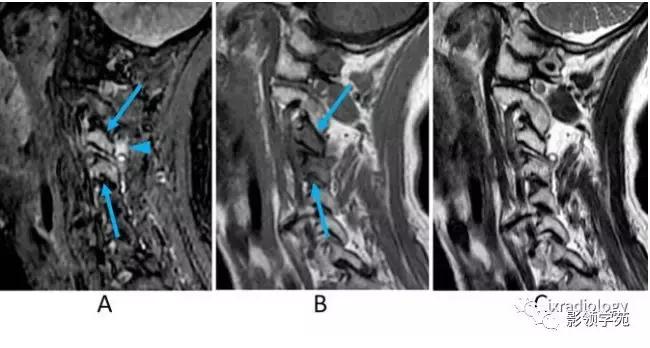

图10:颈椎小关节病。女,60多岁。

A:STIR矢状面图像,B:T1WI矢状面图像,C:T2WI矢状面图像。

MRI图像显示小关节间隙少量积液,提示关节炎。STIR和T1WI显示前后关节突的骨髓水肿(A,B箭)。然而,T2WI很难显示骨髓异常信号,与正常脂肪骨髓信号很难区分。STIR也可见相邻的软组织炎症和/或水肿(A箭头)。